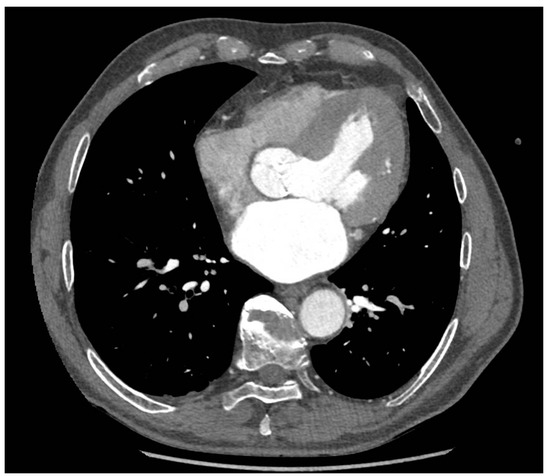

2. Case Report